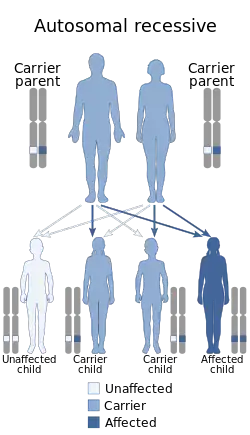

Autosomal recessive osteopetrosis (ARO), also known as malignant infantile osteopetrosis or infantile malignant osteopetrosis (IMO), is a rare type of skeletal dysplasia characterized by a distinct radiographic pattern of overall increased density of the bones with fundamental involvement of the medullary portion. Infantile osteopetrosis typically manifests in infancy. Diagnosis is principally based on clinical and radiographic evaluation, confirmed by gene analysis where applicable.[5] As a result of medullary canal obliteration and bony expansion, grave pancytopenia, cranial nerve compression, and pathologic fractures may ensue. The prognosis is poor if untreated. The classic radiographic features include endobone or "bone-within-bone" appearance in the spine, pelvis and proximal femora, upper limbs, and short tubular bones of the hand. Additionally, there is the Erlenmeyer flask deformity type 2 which is characterized by the absence of normal diaphysial metaphysical modeling of the distal femora with abnormal radiographic appearance of trabecular bone and alternating radiolucent metaphyseal bands.[5]

The various types of osteopetrosis are caused by genetic changes (mutations) in one of at least ten genes. There is nothing a parent can do before, during or after a pregnancy to cause osteopetrosis in a child.[4]

- Mutations in the CLCN7 gene cause most cases of autosomal dominant osteopetrosis, 10-15% of cases of autosomal recessive osteopetrosis (the most severe form), and all known cases of intermediate autosomal osteopetrosis.

- Mutations in the TCIRG1 gene cause about 50% of cases of autosomal recessive osteopetrosis.

- Mutations in the IKBKG gene cause X-linked osteopetrosis.

- Mutations in other genes are less common causes of osteopetrosis.

- In about 30% percent of affected people, the cause is unknown.

Mutations in at least nine genes cause the various types of osteopetrosis. Mutations in the CLCN7 gene are responsible for about 75 percent of cases of autosomal dominant osteopetrosis, 10 to 15 percent of cases of autosomal recessive osteopetrosis, and all known cases of intermediate autosomal osteopetrosis. TCIRG1 gene mutations cause about 50 percent of cases of autosomal recessive osteopetrosis. Mutations in other genes are less common causes of autosomal dominant and autosomal recessive forms of the disorder. The X-linked type of osteopetrosis, OL-EDA-ID, results from mutations in the IKBKG gene. In about 30 percent of all cases of osteopetrosis, the cause of the condition is unknown.[14]